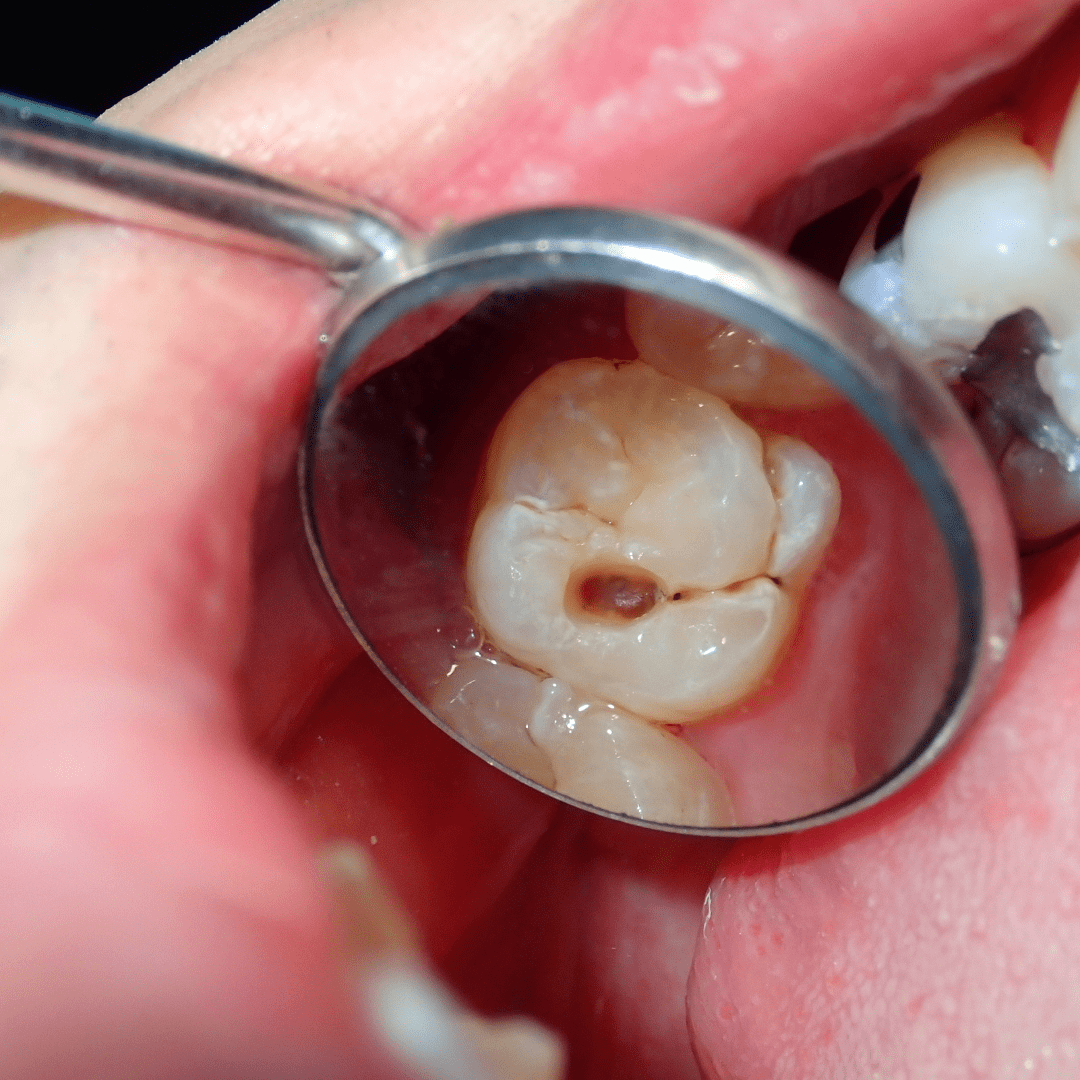

4. Deep grooves or pits in teeth

Molars with deep chewing surfaces can trap food and bacteria, making them more prone to cavities.

Cavities don’t usually cause pain until they reach deeper layers of the tooth — that’s why regular dental exams are so important.

• White or brown spots on the enamel

If decay progresses, you may experience visible holes, persistent toothache, or swelling near the gum line.

At Tooth Harmony, we use visual exams and digital X-rays (when needed) to detect cavities in their earliest stages — long before they cause major damage or discomfort.